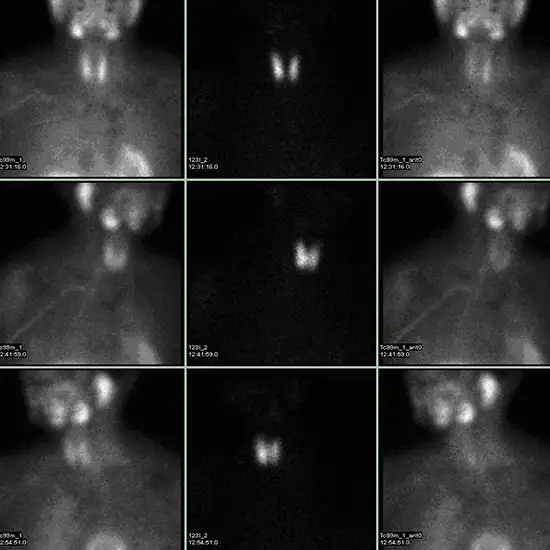

Sestamibi (MIBI) scan

A radioactive chemical (radionuclide) is injected or swallowed in small amounts. Different radionuclides travel to different organs via the bloodstream. A machine equipped with a special camera moves over a person lying on a table and detects the type of radiation emitted by radionuclides.